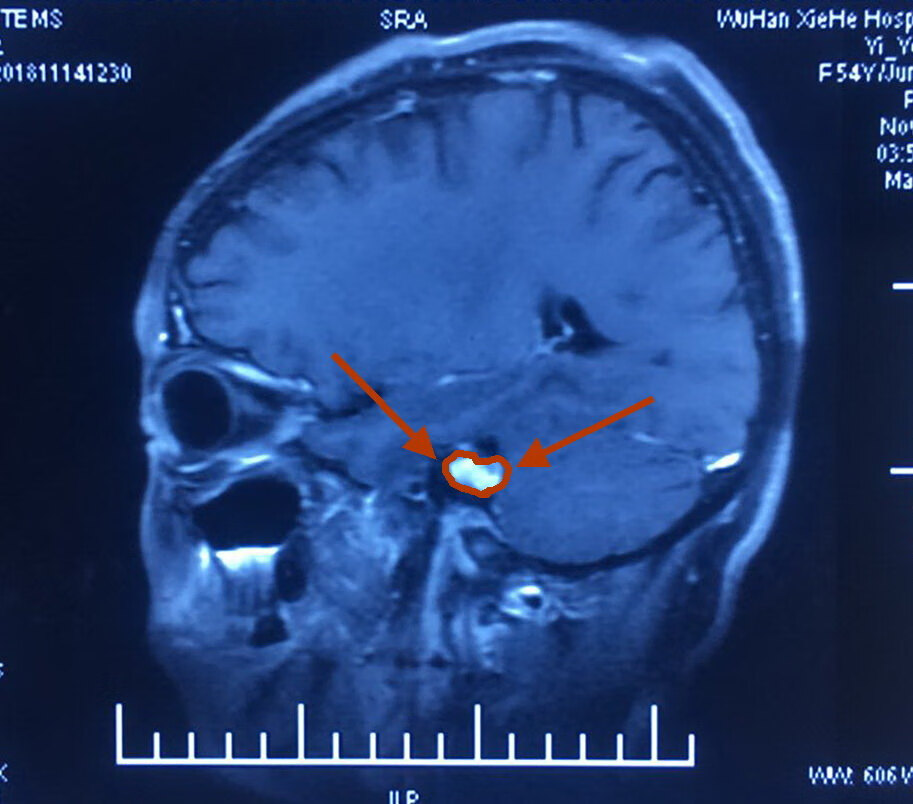

她,45岁,左耳失聪三年。经过核磁共振检查发现左侧桥脑小脑角区占位性病变,考虑听神经瘤。

肿瘤大小1.8cm。

术前影像如下:

采用两端相向汇聚法-显微外科技术切除左侧听神经瘤。

高速磨钻磨开内听道骨性后壁显露面神经内听道端,面神经出脑干端分别显露确认,再瘤内切除减压,两端相向分离肿瘤面神经界面,最后全切肿瘤;术中电生理监测面神经和脑干功能。面神经损伤极小。